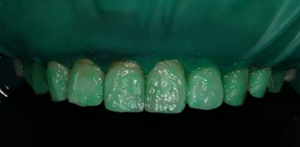

1,術(shù)前照片,全口氟斑牙,前牙表面釉質(zhì)白堊色+黃色斑點(diǎn)+凹坑缺損。

術(shù)前正面?zhèn)让嬲掌?/span>

(下圖是上頜打磨后與下頜術(shù)前未研磨對(duì)比,區(qū)分打磨效果和目的)